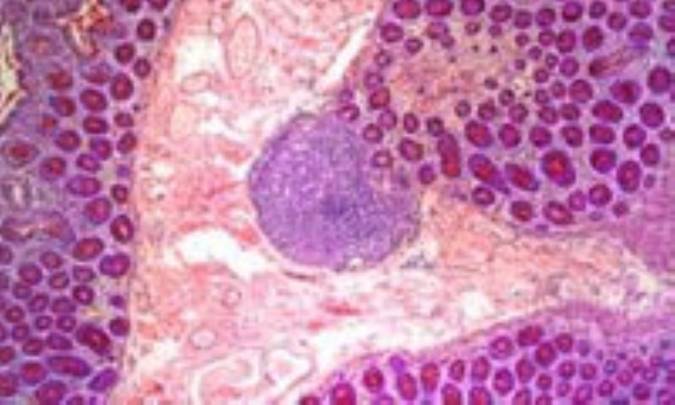

تخمين زده مى‏شود حدود 70% زنان آمريكاى شمالى از تغييرات خوش‏خيم ولى آزار دهنده پستان رنج مى‏برند؛ حساسيتى كه در دوران حاملگى و يا قبل از قاعدگى احساس مى‏كنيد به خاطر سيكل طبيعى هورمون‏هاى جنسى، استروژن و پروژسترون، مى‏باشد. اين هورمون‏ها به سلول‏هاى غدد شيرساز علامت مى‏دهند و باعث رشد آنها مى‏شوند و مناطق اطراف اين غدد همراه با عروق خونى و ديگر مايعات مغذى، افزايش مى‏يابد. اين بافت‏هاى پر از مايع، مى‏توانند فيبرهاى عصبى را تحت فشار قرار دهند و در نتيجه شما احساس درد كنيد.

تغييرات فيبروكيستيك، شامل توده‏ها و كيست‏ها، اغلب مناطق غير فعال را درگير مى‏كنند، مانند سلول‏هاى چربى.